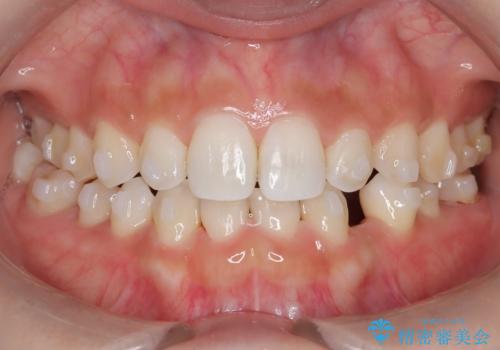

- 空隙歯列を主訴に来院された患者様です。

ばらけている空隙を一箇所に集めながら咬合や正中を改善して最後に補綴治療を行なっています。

右上の臼歯クロスバイトは骨格生のため、そのままにしています。